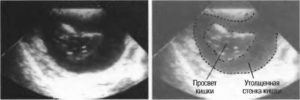

При осмотре области проекции желудка был выявлен симптом поражения полого органа (ППО), свидетельствовавший об утолщении стенок желудка (преимущественно, задней) и сужении его полости в области выходного отдела и тела (рис. 1).

Максимальный наружный диаметр пораженного сегмента желудка составил 54,7; максимальная толщина стенки 28 и протяженность по органу 82 мм. При цветном доплеровском исследовании в области утолщенной стенки были видны хаотично расположенные мелкие сосуды неправильной формы.

После заполнения жидкостью измененная стенка желудка была видна в виде гипоэхогенной, неравномерной, ригидной полосы. Слоистость стенки не выражена, наружные контуры желудка неровные, нечеткие, в области тела по задней стенке и по малой кривизне не просматриваются, сливаются с передней поверхностью поджелудочной железы.

Полость желудка в этом месте сужена, деформирована, перистальтика не прослеживалась. Учитывая интимное прилегание желудка к поджелудочной железе, на фоне заполненного жидкостью желудка, более детально изучена поджелудочная железа.

Рис. 1. УЗИ желудка (исследование натощак).

Эхограмма А. Продольное сечение в эпигастрии левее средней линии. Печень. Поперечное сечение желудка (симптом поражения полого органа). Видно значительное утолщение стенок желудка, преимущественно задней (стенка неровная, нечеткая, сливается с передней поверхностью поджелудочной железы).

Эхограмма B. Косое сечение в эпигастрии. Изображение циркулярно утолщенных стенок желудка в месте их наибольшего утолщения (поражение полого органа).

1 — утолщенные стенки, 2 — суженная полость желудка.